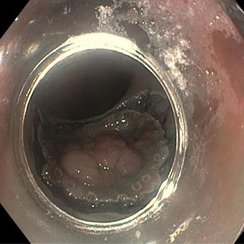

Anschließend wurde der ausgeschaltete Magen mit Flüssigkeit gefüllt und eine Verbindung zwischen dem kleinen Magenrest und dem ausgeschalteten Magen geschaffen (Abbildung 2).

Diese Verbindung wurde mithilfe eines speziellen Metallstents (LAMS, „Hot Axios“) angelegt. Da bei der Patientin keine akute Entzündung der Gallenwege bestand, konnte einige Tage abgewartet werden, bis sich der Stent vollständig entfaltet hatte. Über diesen neu geschaffenen Zugang war es anschließend möglich, die notwendige ERCP durchzuführen und die Gallensteine zu entfernen (Abbildung 3).